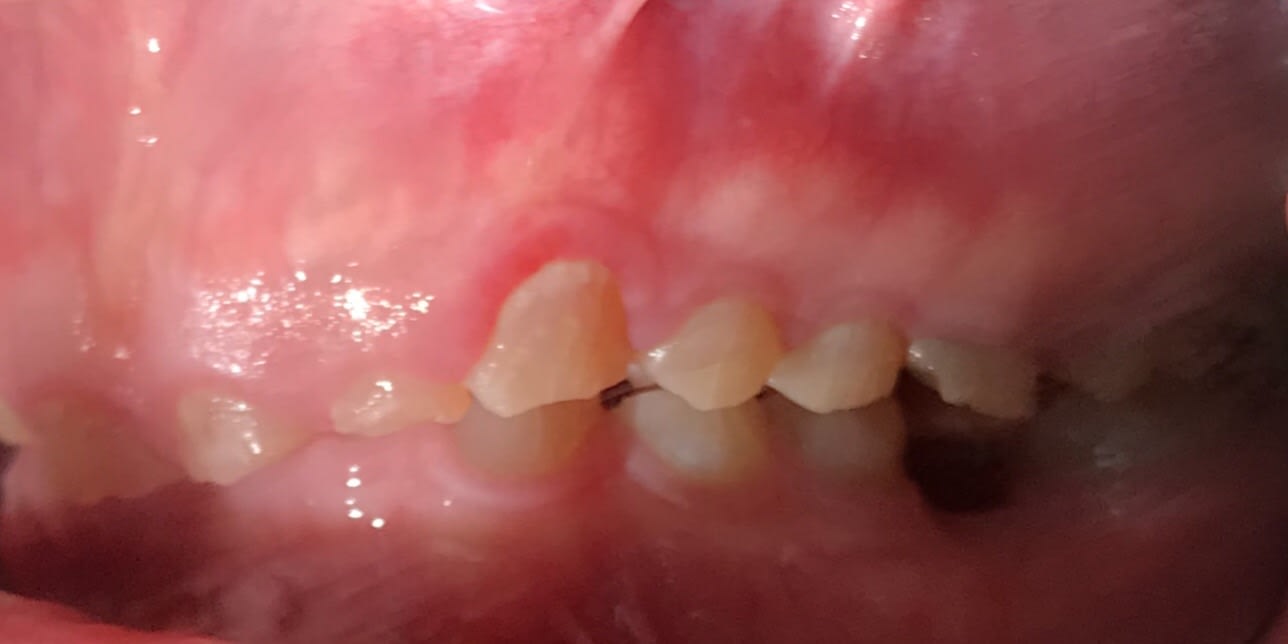

Bonjour je suis lenovo ici . Quelqu’un pourrait-il me donner toutes les étapes pour faire ce cas ? Que faut-il faire précisément ? Le patient n’a pas de contraintes financières. Pas de lésions apicales. Uniquement des usures de dents.

Les photos ne sont pas dingues, mais les usures semblent très majoritairement antérieures. Pourquoi?

Je suspecte un cas d'ortho non traité sous jacent XXL ... que j'aimerais voir sa télé de profil ...

Dentinogenèse imparfaite + bruxisme